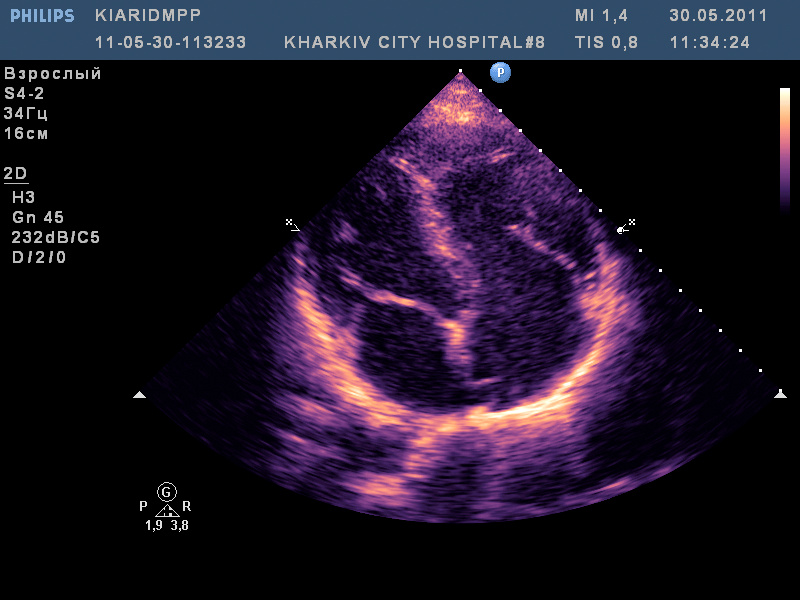

ВПС- высокий дефект межпредсердной перегородки (типа sinus venosus) с наличием аневризмы межпредсердной перегородки и сбросом слева-направо; сеть Киари.